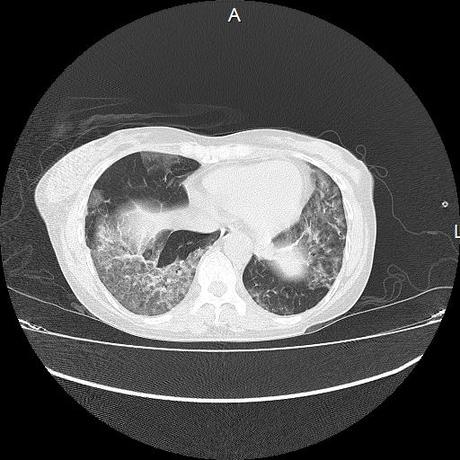

El parénquima pulmonar con areas parcheadas difusas en vidrio despulido combinadas con otras areas hipodensas de baja atenuación debidas a atrapamiento aéreo y engrosamiento intersticial y zonas de fibrosis de predominio en lóbulos medios e inferiores de ambos pulmones.

- LOS HALLAZGOS PUEDEN ESTAR EN RELACIÓN A NEUMOPATIA INTERSTICIAL PROBABLE ETIOLOGIA HIPERSENSITIVA VS AUTOINMUNE/BACTERIANA/FUNGICA.